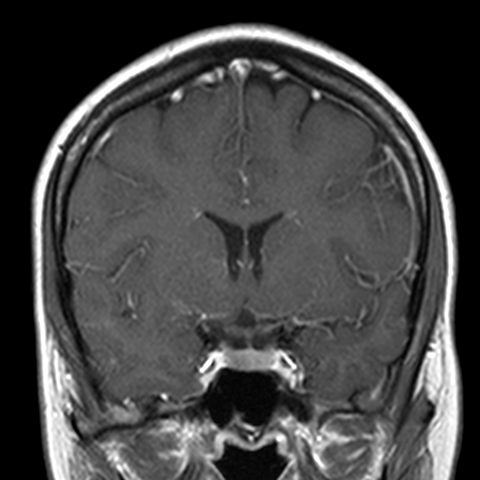

Cranial Meninges (normal) [6 of 8]